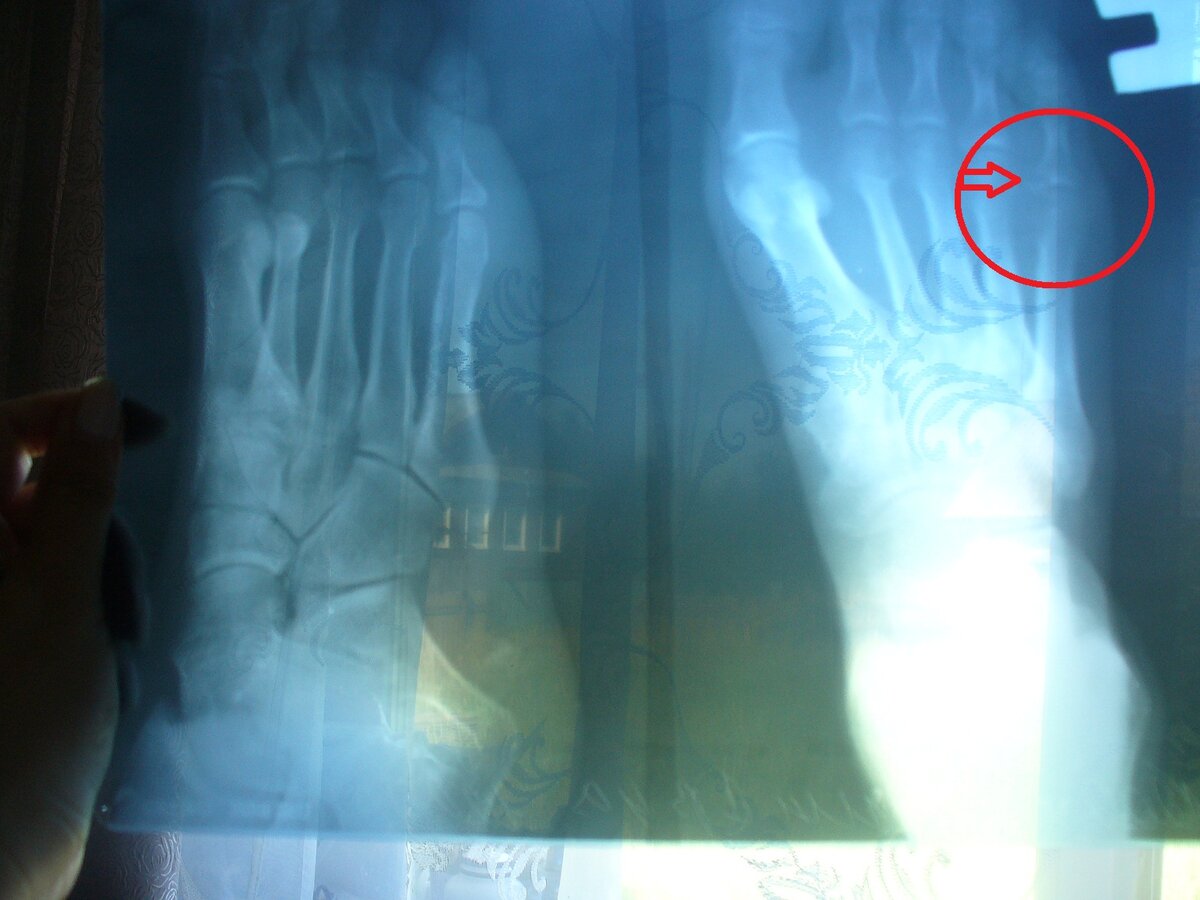

Около девяти утра субботы мы вызвали такси и поехали в приёмный покой. Дождались травматолога, он осмотрел Серёжу, вызвал рентгенолога, сделали рентген стопы... Оказалось, что у мужа перелом. Точнее, у мизинца откололся крохотный такой кусочек кости. На снимке это почти не заметно, но приступать на ногу Серёжа не может от слова совсем: